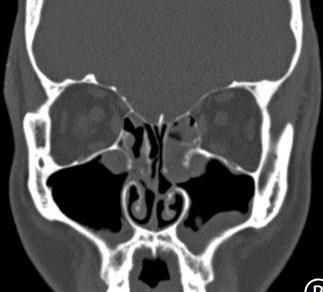

• 术前规范化药物治疗对鼻内镜下慢性鼻窦炎伴鼻息肉患者术后鼻黏膜重塑的影响

摘要:目的 探讨术前规范化药物治疗对鼻内镜下慢性鼻窦炎(CRS)伴鼻息肉(CRSwNP)患者术后鼻黏膜重塑的影响。方法 选取2022年1月-2023年6月该院收治的CRSwNP患者80例,根据随机数表法将患者分为观察组(n = 40)和对照组(n = 40),对照组给予功能性鼻内镜手术治疗,观察组在对照组的基础上给予术前规范化药物综合治疗。比较两组患者鼻腔黏液纤毛清除功能、鼻功能和鼻黏膜重塑变化;采用广义估计方程(GEE)模型,分析其改善情况;采用多元线性回归模型,分析其与各评分之间的关系;采用双重差分模型,分析治疗效果。结果 两组患者组内不同时点(治疗前、治疗后3个月和治疗后6个月)的糖精清除时间、鼻黏液纤毛清除率、黏液纤毛清除速率、鼻腔容积(NCV)、鼻腔最小横截面积(NMCA)、最小横截面积距前鼻孔距离(DCAN)、嗜酸性粒细胞(EOS)、转化生长因子β1(TGF-β1)和血管内皮细胞生长因子(VEGF)水平比较,差异均有统计学意义(F = 124.36,P = 0.000;F = 113.58,P = 0.000;F = 98.67,P = 0.000;F = 87.37,P = 0.000;F = 107.26,P = 0.000;F = 77.45,P = 0.000;F = 3.80,P = 0.008;F = 2.56,P = 0.012;F = 2.13,P = 0.015);观察组治疗后3和6个月糖精清除时间较对照组短,鼻黏液纤毛清除率较对照组高,黏液纤毛清除速率较对照组快,NCV和NMCA较对照组大,DCAN较对照组短,EOS、TGF-β1和VEGF水平较对照组低,差异均有统计学意义(F = 44.36,P = 0.000;F = 38.23,P = 0.000;F = 30.44,P = 0.000;F = 27.33,P = 0.000;F = 36.11,P = 0.000;F = 22.00,P = 0.000;F = 2.44,P = 0.014;F = 1.89,P = 0.017;F = 1.75,P = 0.021);两组患者糖精清除时间、鼻黏液纤毛清除率、黏液纤毛清除速率、NCV、NMCA、DCAN、EOS、TGF-β1和VEGF水平变化趋势比较,差异均有统计学意义(F = 18.33,P = 0.000;F = 15.78,P = 0.000;F = 13.00,P = 0.000;F = 8.17,P = 0.002;F = 10.23,P = 0.000;F = 4.34,P = 0.004;F = 2.89,P = 0.013;F = 1.67,P = 0.022;F = 1.43,P = 0.031)。GEE分析结果显示,观察组鼻黏液纤毛清除率、黏液纤毛清除速率、NMCA、NCV、DCAN和糖精清除时间的改善情况明显优于对照组,差异均有统计学意义(P < 0.05);治疗后6个月,两组患者Lund-Kennedy评分、Lund-Mackay评分和鼻腔鼻窦结局测试-20(SNOT-20)评分明显低于术前,且观察组明显低于对照组,差异均有统计学意义(P < 0.05);多元线性回归模型分析结果显示,糖精清除时间、DCAN、EOS、TGF-β1、VEGF水平、鼻黏液纤毛清除率、黏液纤毛清除速率、NCV和NMCA与Lund-Kennedy评分、Lund-Mackay评分和SNOT-20量表评分密切相关(P < 0.05)。双重差分模型结果显示,观察组Lund-Kennedy评分、Lund-Mackay评分和SNOT-20量表评分的改善情况明显优于对照组。观察组总有效率为92.50%,明显高于对照组的75.00%,差异均有统计学意义(P < 0.05)。结论 在鼻内镜术前采用规范化药物治疗,可以有效地促进CRSwNP患者鼻黏膜修复,抑制术后鼻腔重塑,且疗效较好,值得临床推广应用。